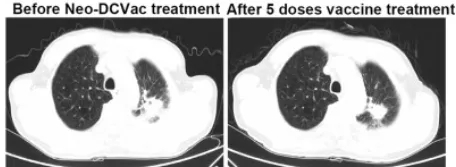

肺腺癌:5剂疫苗注射后肿瘤显著消退

这位幸运的患者既往接受三线化疗和放疗均失败,但在使用Neo-DCVac后7.6个月内未出现任何疾病进展迹象。在五剂个性化Neo-DCVac免疫治疗之前和之后进行CT扫描显示肿瘤靶病灶显著消退。